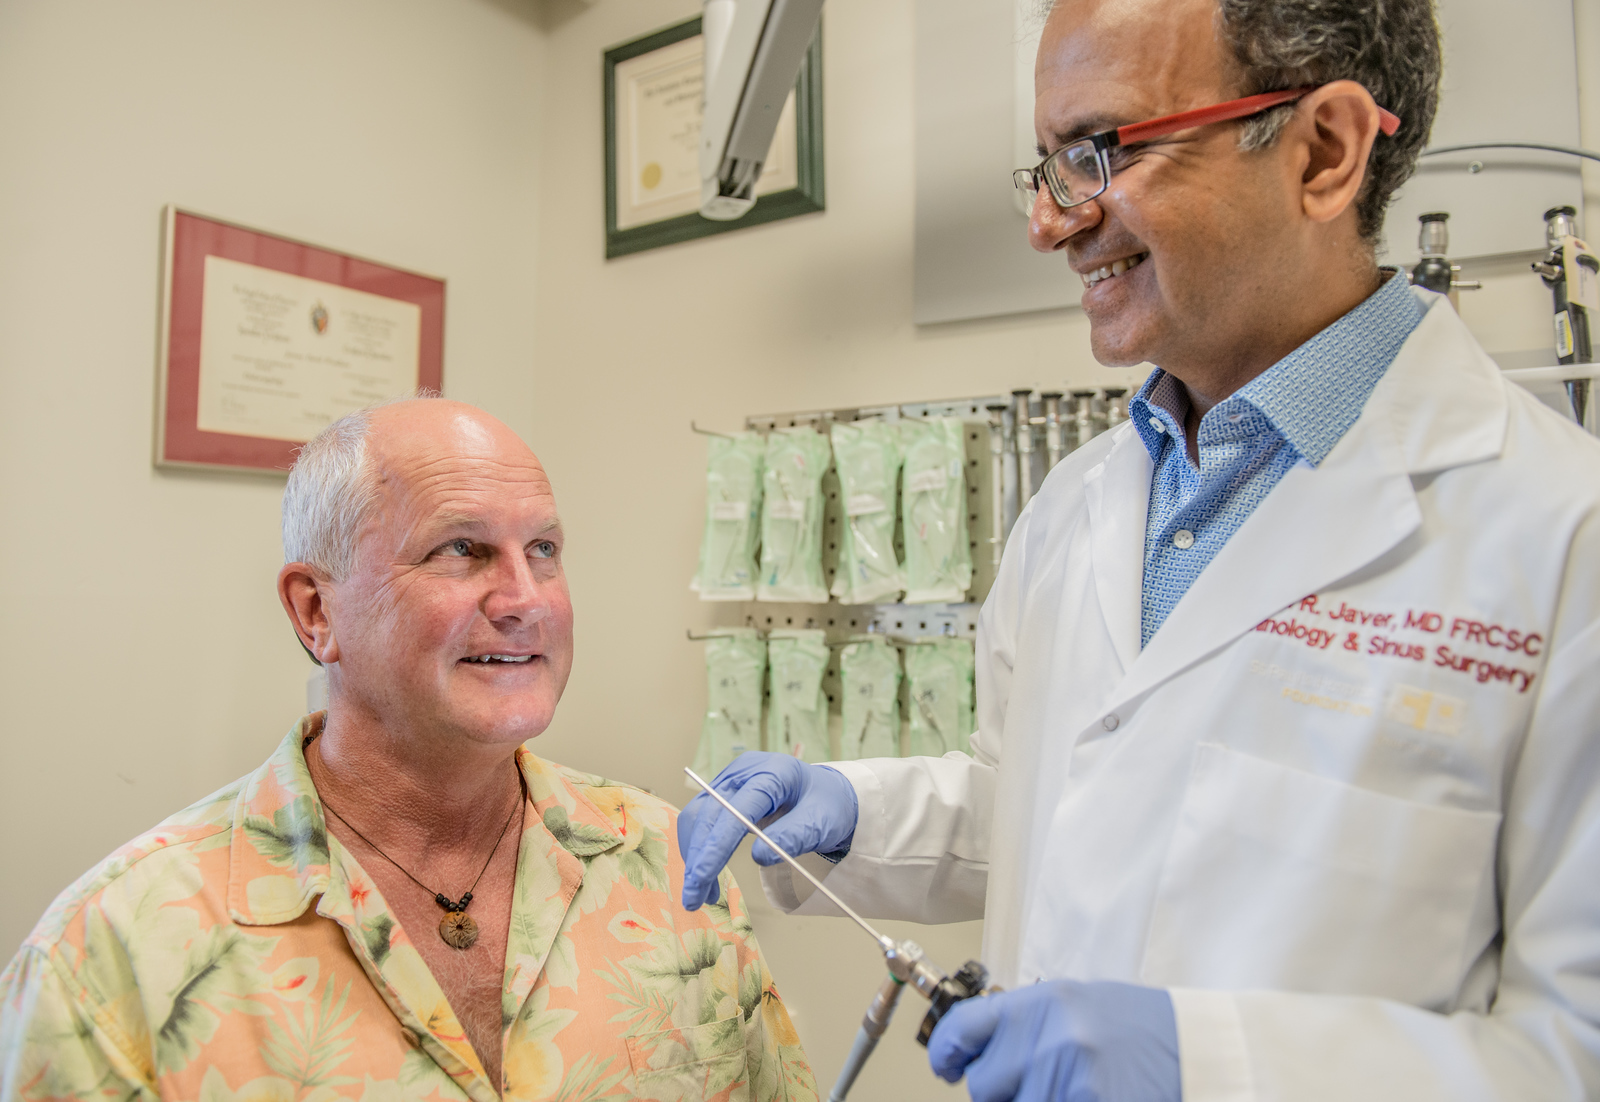

“I’m not just here to add years to your life. I want to improve the quality of your life. So you can speak well, smell the flowers, enjoy your food – all the simple things. ”

Dr. Andrew Thamboo

Rhinologist, Research Director, St. Paul’s Sinus Centre

Dr. Thamboo and his team are working with the BC Cancer Agency to identify blood markers for nasopharyngeal cancer that could detect NPC in its earliest stages.

Read more about NPC and how we’re pioneering new, minimally invasive treatments for NPC and other cancers that disproportionately affect Asian Canadians.